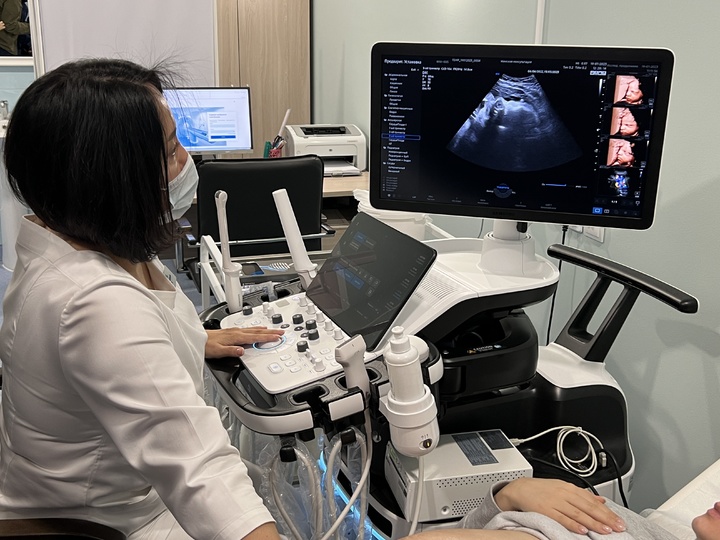

УЗИ аппараты российского производства: обзор и характеристики